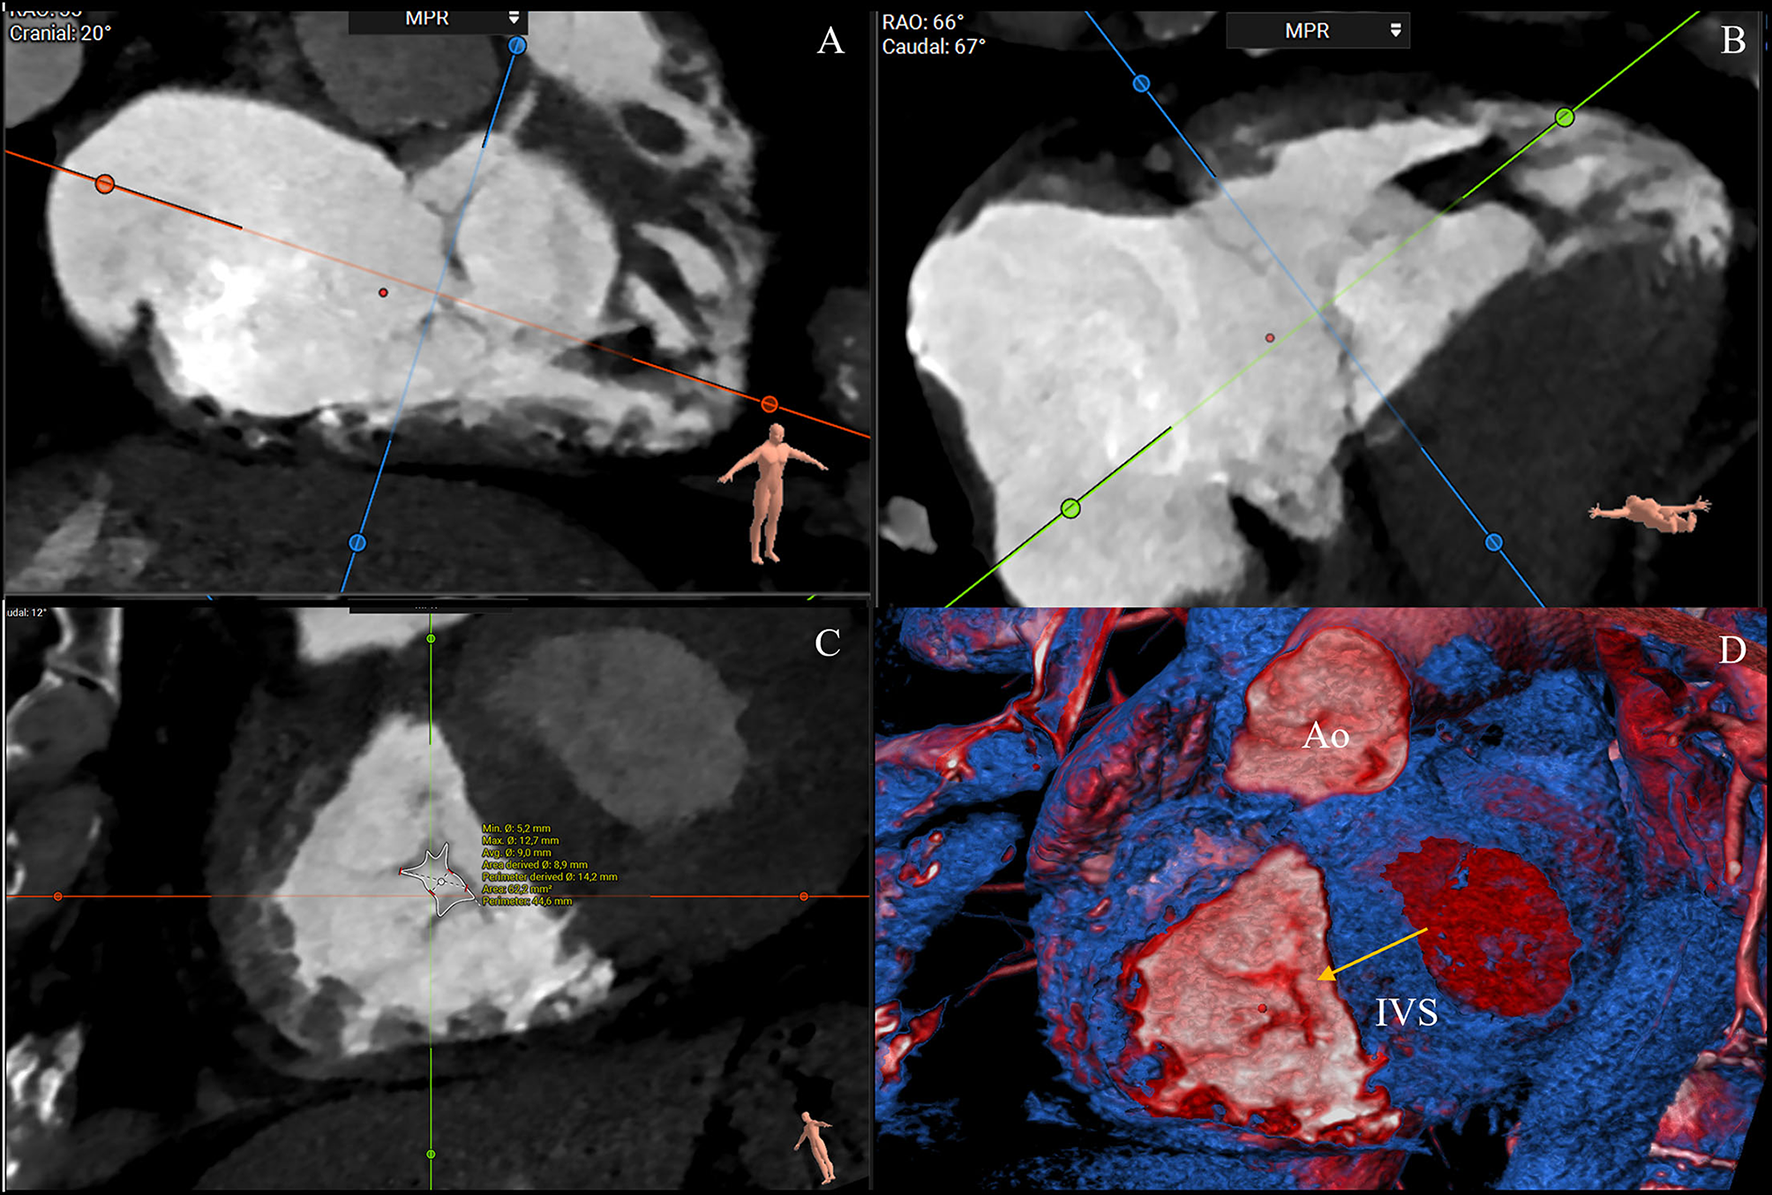

Figure 3

CT multiplanar reconstruction showing the short-axis plane at the annular level (A), the derived four chamber (B), two chamber (C), and volume rendering of the right chambers (D). The annulus septal-lateral diameter is measured in septal to lateral direction (A, blue line) and coincides with the annulus measurement in the four-chamber view (B). The anteroposterior diameter is orthogonal at the previous one (A, orange), and coincides with the measurement in the two-chamber view (C) (3mensio Structural Heart; Pie Medical Imaging, Maastricht, The Netherlands). AP, anteroposterior; SL, septal-lateral.

Additionally, helpful information obtained by CT analysis is the AROA measurement, which may be used as a potential flow-independent anatomic parameter of TR severity, supplementing and enriching the traditional echocardiographic parameters (35, 36). For this purpose, multiplanar reconstruction is performed with the reformation planes aligned with the narrowest portion of the regurgitant orifice during mid-systole and then, the contours of the AROA are manually traced on the short axis (Figure 5) (35). In a recent study by Lopes et al., the tricuspid AROA measurement resulted reproducible, reliably reflected TR severity assessed by TEE, strongly correlated with 3D VCA, and modestly correlated with right-sided chamber remodeling (36).

Figure 5

CT assessment of the anatomical regurgitant orifice area (AROA) using a manual approach. Multiplanar reconstruction is performed with the reformation planes aligned with the narrowest portion of the regurgitant orifice during mid-systole (A,B). Then, the contours of the AROA are manually traced on the reconstructed short axis (C) and tridimensional visualized in the volume rendering apical view (D, arrow) (3mensio Structural Heart; Pie Medical Imaging, Maastricht, The Netherlands). Ao, aorta; IVS, interventricular septum.